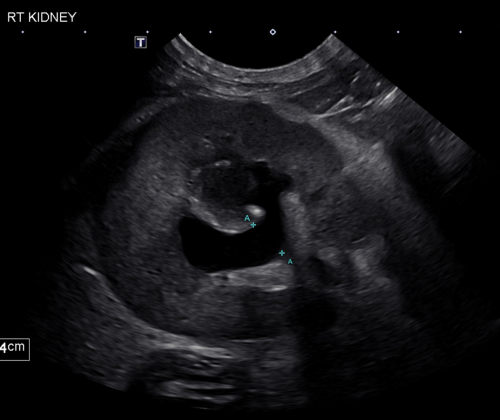

Hosted by the Center for Continuing Professional Education, this interactive mini bootcamp will explore how point-of-care ultrasound (POCUS) is transforming small animal emergency and surgical care. Participants will gain knowledge of how POCUS provides real-time diagnostic insights to support rapid, informed decision-making at the cageside. Core topics include the detection of pericardial, pleural, and abdominal effusion; evaluation of the urinary system; and identification of gastrointestinal abnormalities. A systematic, goal-directed approach will be emphasized to optimize efficiency in high-pressure clinical scenarios.